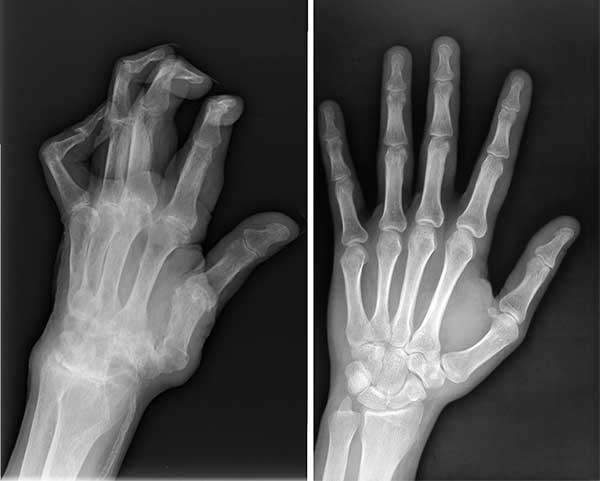

Kondisi lutut saya kala itu. Rasa sakit yang kuat

Di rumah sakit, dokter mengamati hasil rontgen saya cukup lama sebelum akhirnya memberi tahu bahwa saya tidak boleh lagi melakukan pekerjaan fisik berat atau mengangkat beban lebih dari 2 kilogram.

X-ray menunjukkan masalah serius dengan lutut saya

Rontgen suami sebelum dan sesudah mengonsumsi Invanil

Keadaan tangan suami saya sebelum dan sesudah mengonsumsi Invanil